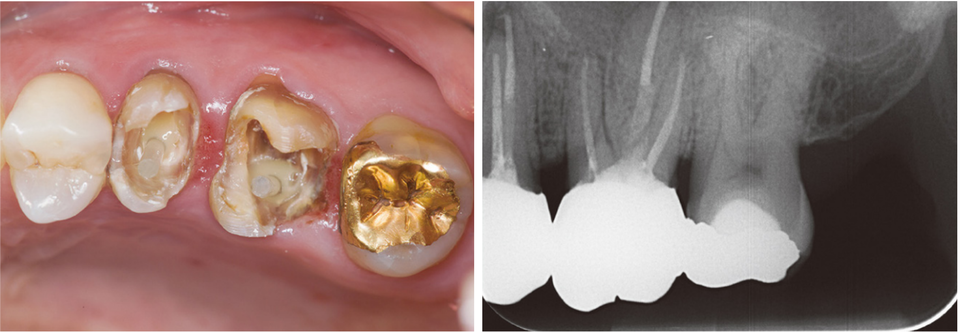

#14~#16 레진 충전

왜 이런 과정을 사진으로 기록할까? 개원한 치과의사는 누구의 간섭도 받지 않고 자신의 양심과 임상능력을 따라 진료한다. 임상 과정을 사진으로 기록하고 정리하는 과정에서 자신의 부족한 점이 드러난다. 최종 치료결과가 좋을 때는 자신감과 직업적인 보람을 얻기도 한다.